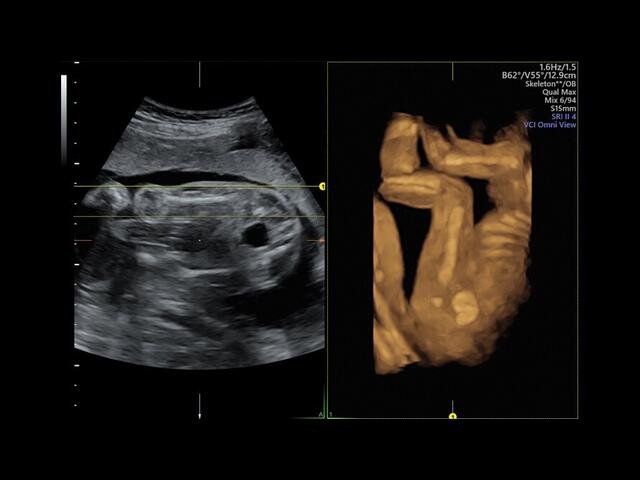

Система GE Voluson E8 обладает значительной вычислительной мощностью, которая позволяет решать даже самые сложные задачи в области диагностики плода. Она отличается высоким уровнем качества и статусом, предоставляя врачу потрясающие изображения во время 2D/3D-исследований. Кроме того, система всегда готова к использованию режима 4D благодаря чувствительному цветному доплеру.

• Технология контрастной 3D-визуализации VCI для повышения качества изображений в одной и трех проекциях.

• Режим ультразвуковой томографии TUI для одновременного просмотра нескольких параллельных срезов в режиме реального времени и кинопетли.